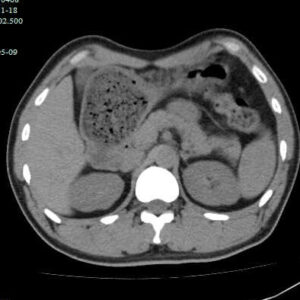

最近有几个吃山楂后形成胃结石的病历,第一个,老年女性,突发腹痛2天,持续性钝痛,阵发性加重,伴恶心,呕吐胃内容物,性状无异常,呕吐后无缓解,入院后抑酸治疗效果不理想,CT如下图。

因为非影像专业,自己总结肠道植物性结石的特点,混杂密度,多数边缘规则,与正常胃、肠壁结构分界清晰,临床考虑多数急性起病,关键是要问近期是否有大量食用柿子、山楂、黑枣等富含鞣酸食物。